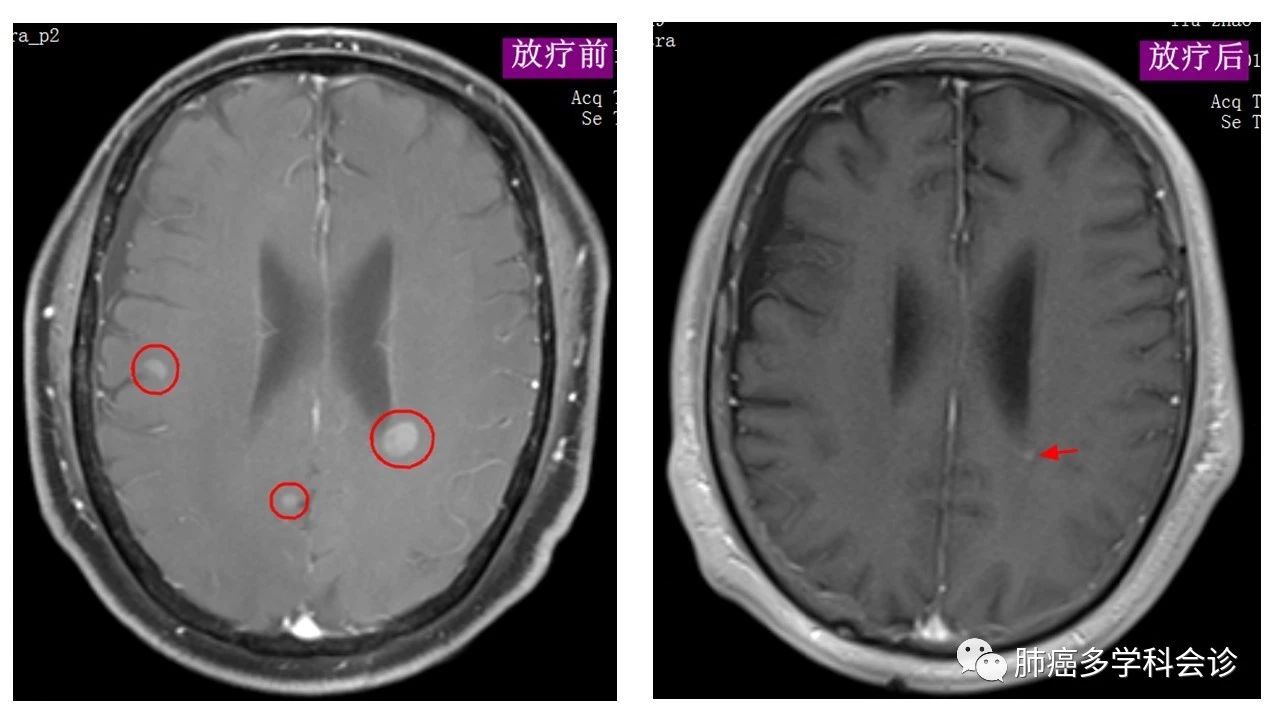

刘某某,男,53岁,患左肺小细胞肺癌局限期,接受“”铂+依托泊苷“化疗和胸部放疗。之后不久发现脑内多发转移,再行脑部放疗,脑转移灶得到控制。下图为该患者的多发脑转移灶在放疗前、后的 MRI 图像,放疗后(WBRT+SRS)转移灶基本消失: